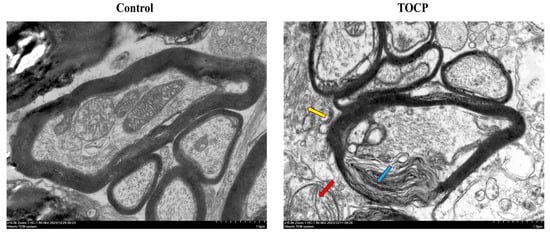

2.2. Transmission Electron Microscopy (TEM)

3.1. TOCP-Induced Neurotoxicity in Adult Hens

- Xin, X.; Zeng, T.; Dou, D.D.; Zhao, S.; Du, J.Y.; Pei, J.J.; Xie, K.Q.; Zhao, X.L. Changes of mitochondrial ultrastructures and function in central nervous tissue of hens treated with tri-ortho-cresyl phosphate (TOCP). Hum. Exp. Toxicol. 2011, 30, 1062–1072. [Google Scholar] [CrossRef] [PubMed]